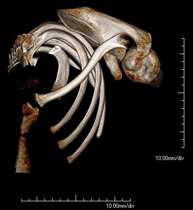

- TC Parrilla costal Exploración radiológica que mediante un sistema de rayos X y detectores que giran alrededor del paciente, reconstruyendo las imágenes por ordenador, permite el estudio detallado de la parrilla costal. Exploración radiológica que mediante un sistema de rayos X y detectores que giran alrededor del paciente, reconstruyendo las imágenes por ordenador, permite el estudio detallado de la parrilla costal.

- Osteoarticular- TC Hombro Exploración radiológica que mediante un sistema de rayos X y detectores que giran alrededor del paciente, reconstruyendo las imágenes por ordenador (TC Multidetector), permite el estudio de huesos, músculos y articulaciones del hombro. Exploración radiológica que mediante un sistema de rayos X y detectores que giran alrededor del paciente, reconstruyendo las imágenes por ordenador (TC Multidetector), permite el estudio de huesos, músculos y articulaciones del hombro.